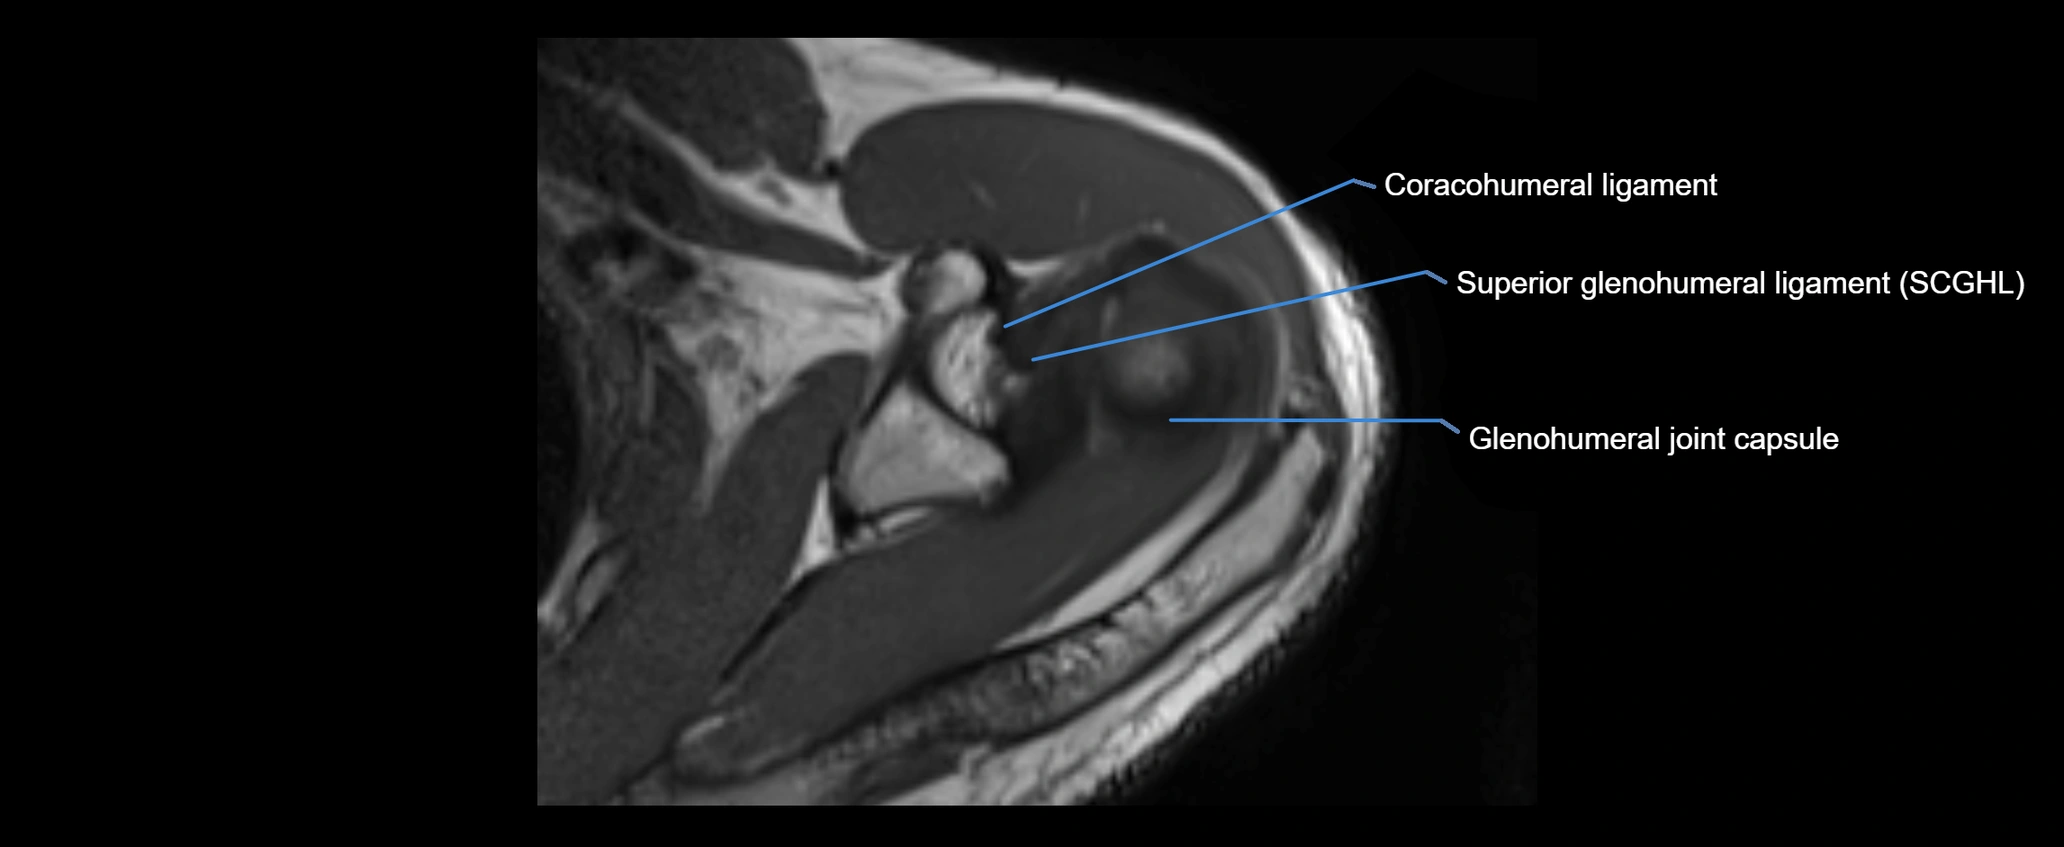

CT image

image